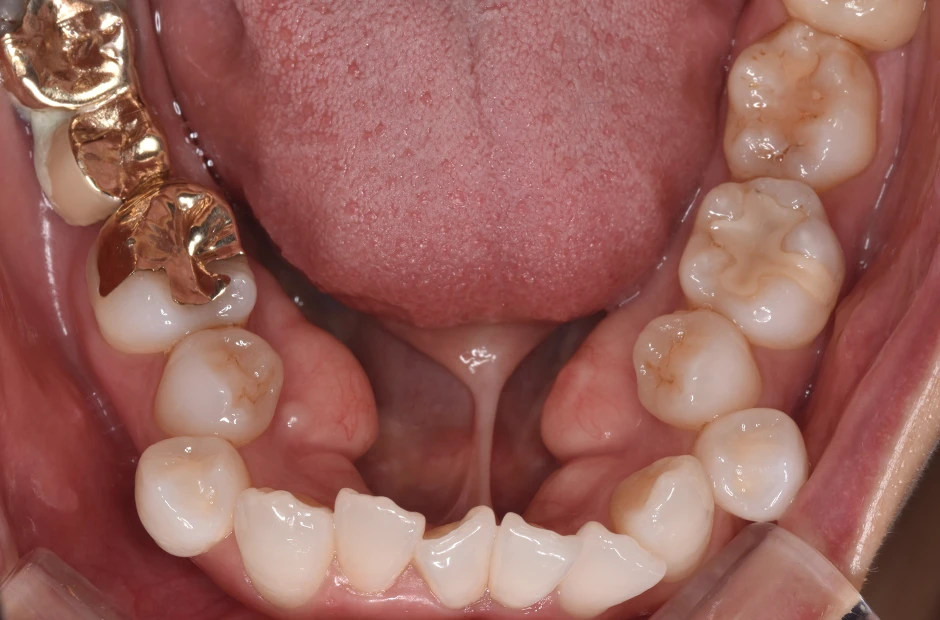

叢生

| 診断名・主訴 | 叢生 |

|---|---|

| 年齢・性別 | 43歳・女性 |

| 治療期間・回数 | 2年7か月 27回 |

| 治療に用いた主な装置 | 舌側矯正 |

| 抜歯部位 | 両顎4,4 |

| 治療費 | 100万円(税抜) |

| リスク・副作用 | 装置による違和感・疼痛・歯肉退縮・歯根吸収・虫歯のリスクなど |

治療前

治療後